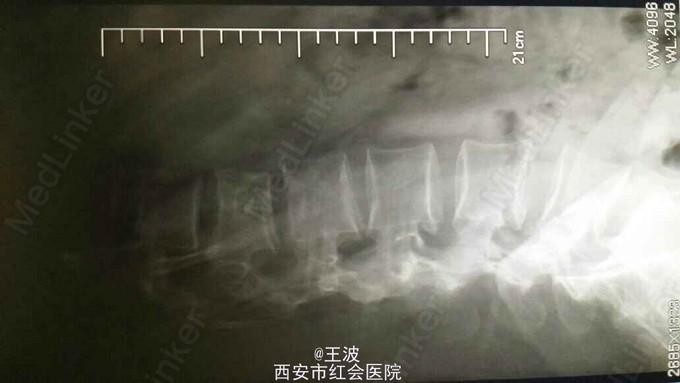

患者3年前外伤后腰1 2椎体爆裂骨折伴神经不全损伤,行胸12腰1椎板切除减压内固定,术后仍下肢麻木,左下肢无力,现拟取出内固定

查体:脊柱生理弯曲存在、无畸形、活动正常、局部皮下可触及金属内固定物、左侧足踝背伸减弱、肌力III级,膝以下平面感觉麻木、生理反射存在、右侧背伸减弱、肌力IV级.腰椎CT示腰椎骨折金属内固定术后状,未见明显脱位,椎间隙积气

患者神经损伤为陈旧性,已经不能完全恢复,即使术后取出内固定,下肢功能也不能恢复。术后X片显示:腰1椎体楔形改变、椎体内见高密度影、腰2椎体两侧不等高、腰1椎体缺如、椎间隙未见异常